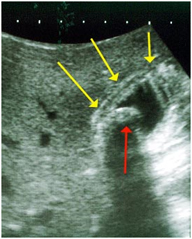

La universitaria realizó un trabajo de investigación prospectivo de corte transversal en el personal de blanco del Hospital Regional de Encarnación (HRE), con una muestra de 55 funcionarios a los cuales se les realizo una ecografía abdominal, se encontró a 3 personas con litiasis vesicular asintomática, lo que representa una prevalencia de 5,45 %. Esta cifra es inferior a la que se menciona en la literatura que ronda el 10 %, pero resalta el estudio que la población estudiada correspondía a la segunda década de la vida y esto explicaría el bajo porcentaje, ya que la frecuencia aumenta en relación lineal con la edad.

El sexo de mayor prevalencia era el femenino con un 67 %, el mismo porcentaje de pacientes era de Encarnación y padecía de sobrepeso. Un dato muy importante es que ninguno de los pacientes con litiasis realizaba actividad física.